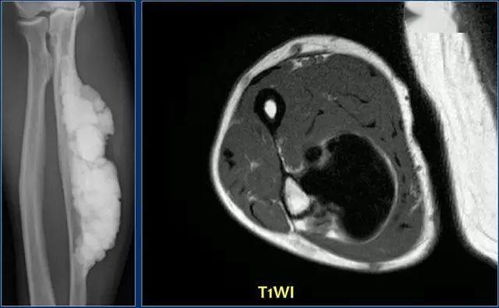

对于疑似肺部肿瘤导致的胸痛,诊断是关键。影像学检查,特别是CT扫描,是识别肺部肿瘤的重要工具。通过CT,我们可以观察到结节或肿块的形态,如分叶、毛刺征等特征。肿瘤标志物的检测,如CEA(癌胚抗原),也是辅助诊断的重要手段。但需要注意的是,肿瘤标志物的升高并不一定意味着晚期肺癌,还需要结合其他检查和症状进行综合判断。